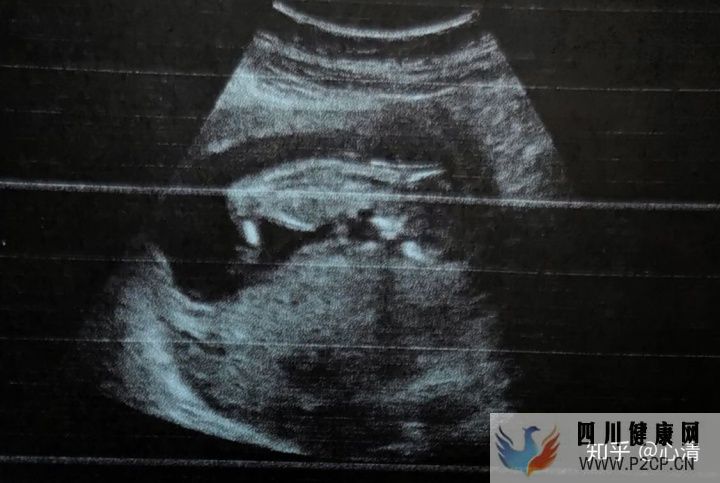

2020.6.9,孕22周+,b超大排畸,早上吃完饭带了威化、巧克力、甜饮料去医院,想着万一宝宝做b超时候不动医生看不全器官,可以随时吃点甜的让宝宝动起来,结果医生非常专业,找角度戳肚子拍打,十分钟大排畸就完成了,一切正常,宫颈长3.9cm。21周的b超胎儿还是头位,22周就变成臀位了,可能肚子里空间大,游来游去不受阻碍吧。

2020.6.13,孕23周+,预约了在外面做四维彩超,第一次在屏幕上看到动态的宝宝(三甲医院的b超屏幕在头顶,什么都看不见),老公也一起进来看到了,感觉好幸福。送了10张左右照片+一段小视频。送了粉色相框哦~闺女棒棒哒!